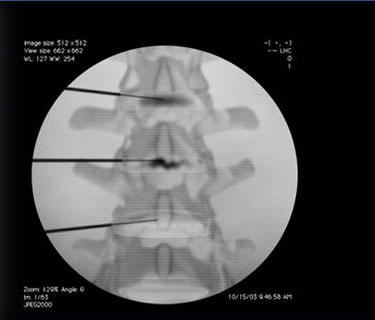

- Caudal Steroid Injection

- Facet Joint Injections

- Joint Steroid Injection

- Spinal Cord Stimulator Implant

- Discography

- Lumbar Epidural Steroid Injection

- Medial Branch Block